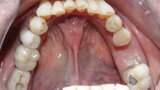

Figure 21 Palatal view of upper anterior emax 2 layered restorations all veneers except 21